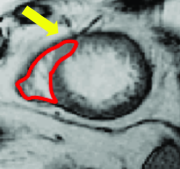

Appearance is one of the most important visual cues to distinguish between different structures in an image. Appearance is described by studying the distribution of different features such as intensity values in gray-scale images, color, and texture inside each object. In most cases, appearance models are incorporated into the data term in (2) and (7). The purpose of incorporating appearance prior is to fit the appearance distribution of the segmented objects to the distribution of objects of interest, e.g. using Gaussian mixture model (GMM) (Rother et al., 2004). In the literature, there are two ways to model the appearance: 1) adaptively learning the appearance during the segmentation procedure, and 2) knowing the appearance model prior to performing segmentation (e.g. by observing the appearance distribution of the training data). In the former case, the appearance model is learned as the segmentation is performed (Vese and Chan, 2002) (computed online). In the second case, it is assumed that the probability of each pixel belonging to particular label is known, i.e. if represents a particular set of feature values (e.g. intensity/color) associated with each image location for object, then it is assumed that is known (or pre-computed offline). This probability is usually learned and estimated from the distribution of features inside small samples of each object. Figure 9 illustrates the probability of different structures (the kidney, the tumour, and the background) in an endoscopic scene. A lower intensity in Figures 9(b-d) corresponds to higher probability.

More advanced texture features such as those based on Haar and Gabor filter banks have shown many successes in medical image segmentation (Huang et al., 2005; Malcolm et al., 2007; Santner et al., 2009). Koss et al. (1999) and Frangi et al. (1998) are two works that utilized advanced features to segment abdominal organs and to measure vesselness, respectively. In (Frangi et al., 1998), the eigenvalues of the image Hessian matrix are used for measuring the vesselness of pixels in images. This measure is used for liver vessel segmentation both in a variational framework (Freiman et al., 2009) and in a graph-based framework (Esneault et al., 2010). Statistical overlap prior is another strong appearance prior that has been proposed by Ayed et al. (2009). Their method embeds statistical information (e.g. histogram of intensities) about the overlap between the distributions within the object and the background in a variational image segmentation framework. They used the Bhattacharyya coefficient measuring the amount of overlap between two distributions, i.e. if . Ben Ayed et al. (2009) used this strong prior to segment left ventricle in MR images.